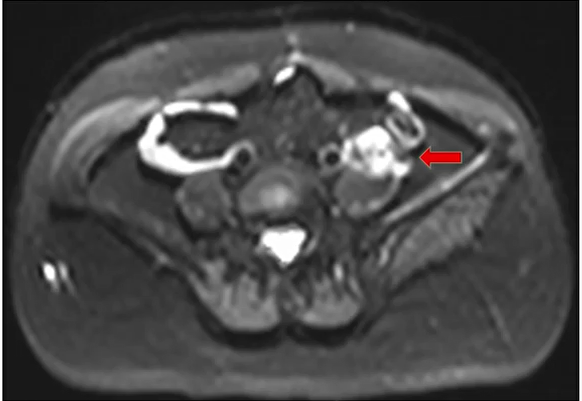

术前全腹部MRI增强提示:左侧腰大肌旁复发性淋巴结。

2023-06全腹部MR提示左肾门腹主动脉旁淋巴结转移;

2024-07-22 CA125:52U/L,全腹部CT提示:左骼总动脉左肿大淋巴结;